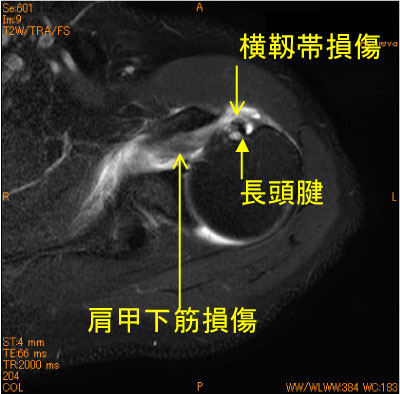

亜脱臼後変化(肩甲下筋損傷、他)-肩関節MRI-

肩甲下筋損傷、結節間溝横靭帯損傷、関節液貯留、腱板疎部損傷による烏口下滑液包と関節腔の交通、関節上腕靭帯の上腕骨頭側での断裂を認めている(HAGL)。

亜脱臼後の多彩な変化である。外傷ではありとあらゆくことがおこりうる。

![]() Axial T2WI 脂肪抑制 |